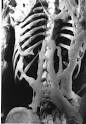

La Fibrodisplasia Osificante Progresiva o FOP "es un raro desorden genético que causa que hueso se forme en los músculos, tendones, ligamentos y oros tejidos conectivos. Puentes de hueso extra se desarrollan a través de las articulaciones, restringiendo progresivamente el movimiento. En FOP, el cuerpo produce no sólo mucho hueso, sino un esqueleto extra que encajona al cuerpo, encerrando a la persona en una prisión ósea de la cual no hay llave", explica la Asociación Internacional de Fibrodisplasia Osificante Progresiva , IFOPA. Sólo una cada dos millones de personas la padecen; por lo que se estiman 2.500 casos en todo el mundo de los cuales se conocen sólo 400. En Argentina se calcula que podría haber cerca de 20, de los cuales un poco más de una docena están identificados.

Quizá el caso más conocido de FOP en tiempos modernos sea el de Harry Raymon Eastlack Jr., nacido en Filadelfia, PA en noviembre de 1933. Su condición comenzó a desarrollarse a la edad de diez años y para la época de su muerte por una neumonía en noviembre de 1973 (seis días antes de su cuadragésimo cumpleaños), su cuerpo se había osificado por completo y sólo podía mover sus labios.

Lo que hace al caso de Eastlack particularmente notable es que antes de su muerte hizo conocer su intención de donar su cuerpo a la ciencia, con la esperanza de que su muerte pueda ayudar a encontrar una cura a esta poco entendida y particularmente cruel enfermedad. Como era su deseo, su esqueleto preservado ahora reside en el museo Mütter (ver animación), en el Colegio de Medicina de Filadelfia y fue una invalorable fuente de información para el estudio de esta enfermedad.